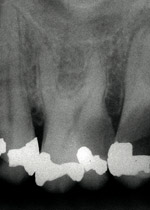

Figure 1 shows a radiograph of a typical maxillary first molar. Upon extraction, the apical anatomy was immediately studied and photographed under a global microscope (Figure 2, Figure 3, Figure 4, Figure 5 and Figure 6). That is a take-home lesson; the extracted teeth should be studied with loupes or microscopes. These photographs demonstrate an important lesson. The two-dimensional radiograph shows three roots. In reality, however, a significant percentage of maxillary first and third molars—80% in some studies—have four roots and four or more canals. 1,2 While the MB and MP (MB-2) roots are usually fused, their morphology is unique. For diagnostic, access, and shaping purposes, it is safer to think of them as separate roots. Wisdom teeth often exaggerate the anatomic features of first and second molars, and a significant percentage of maxillary third molars have four distinct roots. The author's personal bias is to consider most maxillary first the radiographic apex of the tooth. The use of the radiographic root apex for use as the reference point for measuring the apical extent of the root filling is the common standard, yet has been criticized because of the poor correlation between the location of this point and the actual canal foramen. 5 The illustrations used in advertising and manufacturer's "tip cards" only further the notion of simple foramen anatomy. While simple anatomy is often the case with incisor teeth, a quick perusal of the posterior teeth in Brown and Herbransen's Dental Anatomy & 3D Interactive Tooth Atlas demonstrates that a significant portion of the foramen exit short of the apex and have multiple foramina. 6 The same extracted tooth in Figure 2 demonstrates that the palatal foramen is more than a millimeter short of the radiographic apex. If this tooth were filled to the constriction, which for arguments sake is 0.75 mm from the foramen, a straight-on radiograph would depict the fill as being at least 2 mm "short."

Fig. 1 Periapical radiograph of maxillary left first molar. Two-dimensional images lead to two-dimensional thinking.

Figure 1